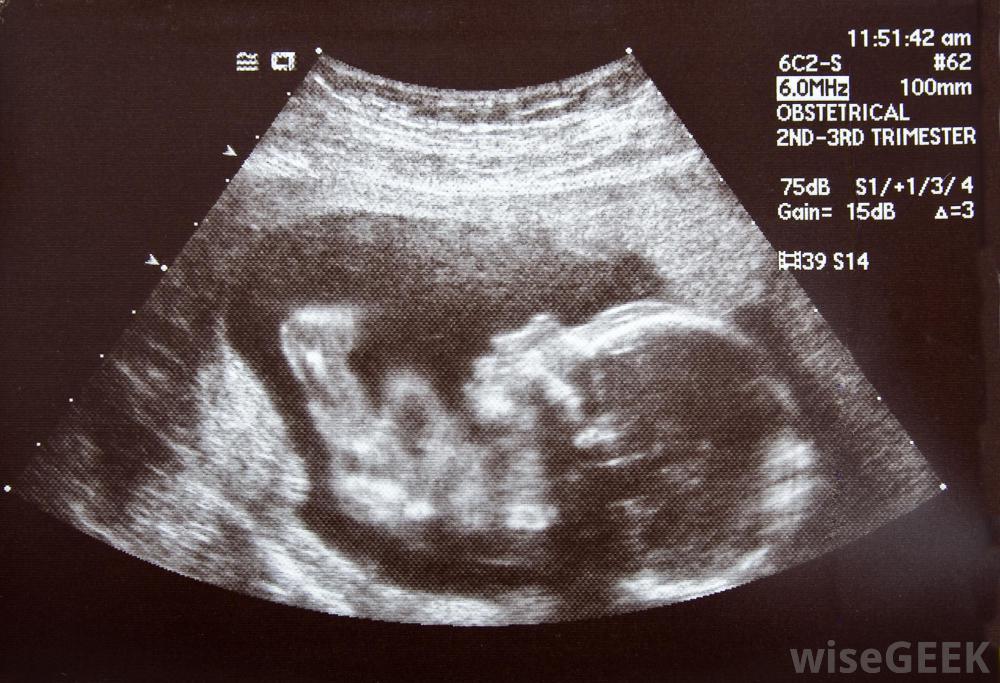

怀孕28周后,可进行压力测试,以评估胎儿的健康状况。当妇女有高风险怀孕时,当医生担心时,通常推荐胎儿NST胎盘,或当妇女注意到胎儿活动比平时少时。这种检查是无创性的,没有风险。胎儿NST可以在诊所或医生办公室进行,为了方便起见,可以在预约定期产前检查时进行

a胎儿NST可作为常规产前检查的一部分进行。医生可能会建议在怀孕期间进行多次胎儿NST检查,以监测母亲和胎儿如果观察到异常情况,可以利用超声波和其他检测方法来了解胎儿为什么没有反应,随着时间的推移,女性往往会了解胎儿的生活习惯,如果胎儿似乎不如平时活跃,最好打电话给医生,讨论可能的原因,并做好预约就诊的计划